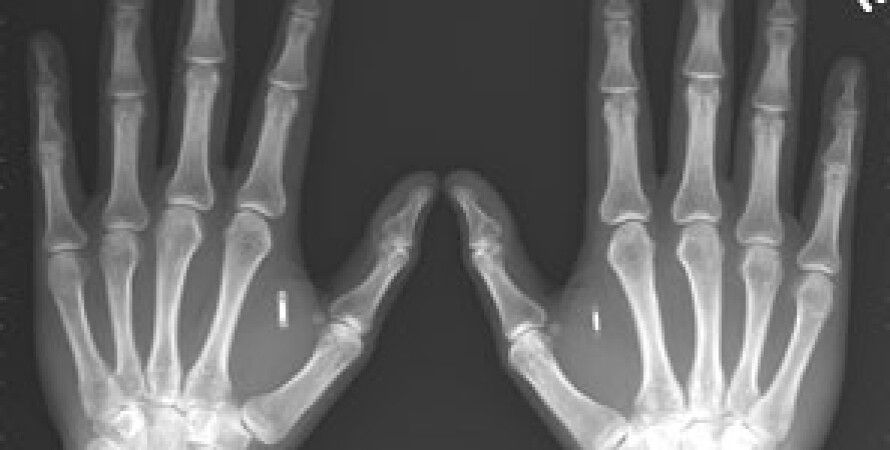

Руководивший трансплантацией хирург Эдгар Бимер, больному предстоит длительный курс восстановительной физиотерапии. В частности, по прогнозу специалиста, почувствовать пальцы вновь обретенных рук он сможет приблизительно через два года, сообщает Lenta.ru.

Врачи также не исключают возможности отторжения трансплантатов. Дополнительные проблемы создает большая разница в возрасте между пациентом и донором: пока не известно, как скажется на психологическом состоянии больного наличие рук 19-летнего юноши.